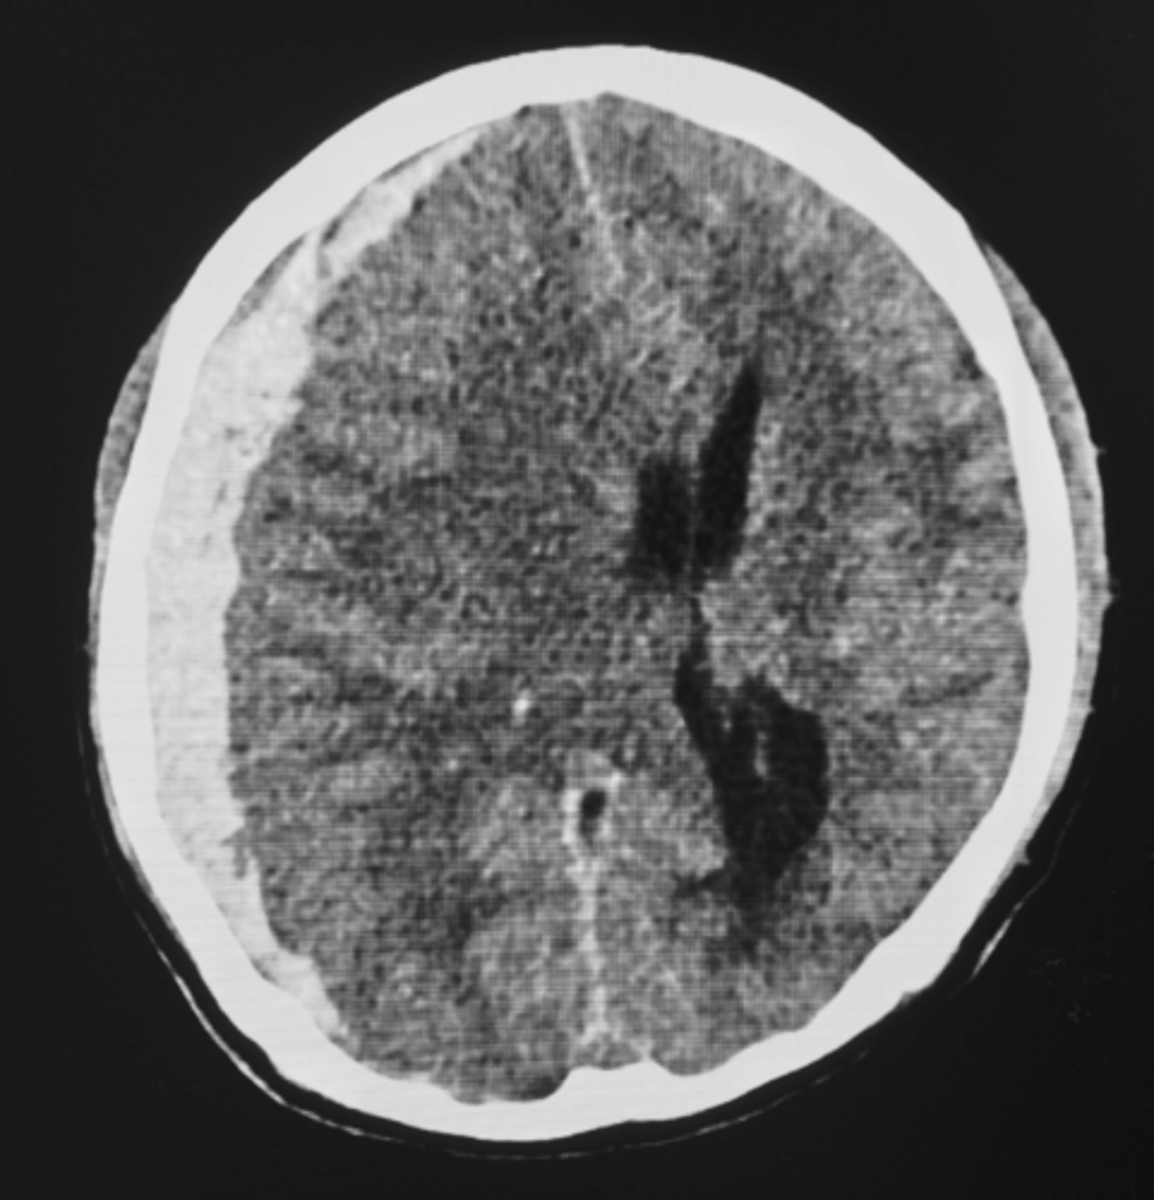

Subdermal Hematoma

- Between dura and arachnoid mater

- Tearing of bridging veins (alcohol use and older population)

- Acute or subacute neurological symptoms

- Neurosurgery consult, BP control, reverse anticoagulation